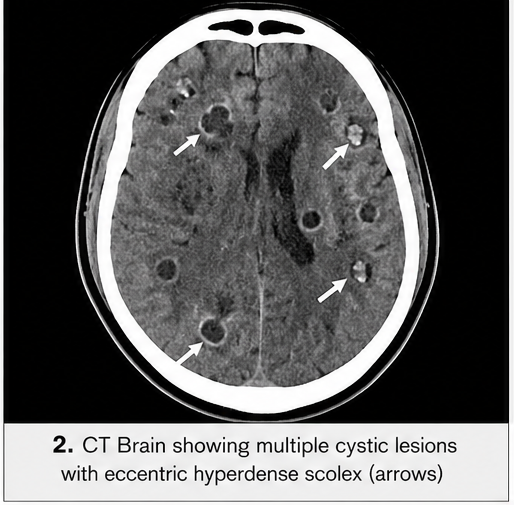

CT Scan of the Brain

• Multiple small cystic lesions in the cerebral cortex

• Some lesions showed eccentric hyperdense nodules (scolex)

• Surrounding perilesional edema

These findings were highly suggestive of neurocysticercosis.

Characteristic imaging findings include:

• Cystic lesions with scolex